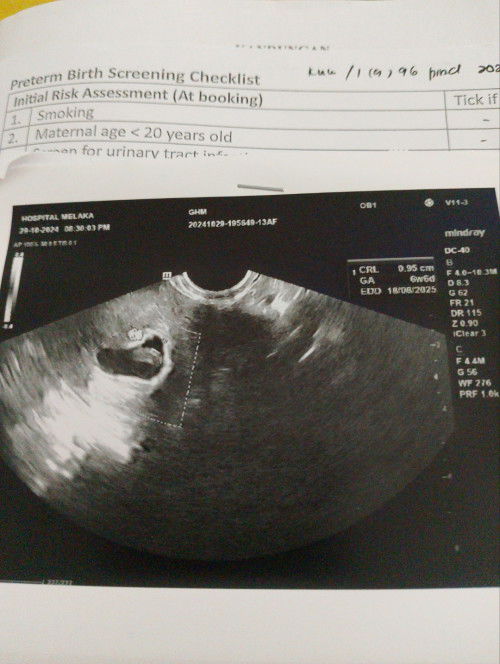

Assalamualaikum mami semua.. nk tnye ad x sama kes mcm sy? Lau ikut period 12/8 so patut la ni 11w1d dah.. tp bila scan tvs(melalui bwh)dpt usia 6w6d dan ad janin dlm kantung cuma janin tu lum nmpk heartbeat.. ke mmg usia 6w ni janin xnmpk denyut jantung lg? Nti lg 2minggu kene repeat scan lg kat o&g . Sy risau, takut janin sy masih sama x mbesar selepas 2minggu nti🥲tp td kat kk pun scan kot atas mmg nmpk tarikh 6w jugak.. kat spital pakar pun dpt 6w jugak adakah btul kandungan sy 6w? Dan bukan 11w? Allah

Baca lagiHi sis. Sama macam saya, kalau period sis tak regular memang tak boleh ikut LMP yaa. Kena ikut scan & benda tu normal. Nanti sis scan lagi 2 weeks, kalau dia membesar bersesuaian dengan date scan, insyaAllah takde apa sis. 6w kadang memang belum nampak heartbeat. Macam saya patut ikut LMP haritu dah 7w, tapi pergi scan swasta rupanya baru 4w & memang tak nampak apa apa. Saya repeat scan lepas 2 minggu, alhamdulillah dah nampak janin & hearbeat kelip kelip. Masatu usia kandungan saya 6w6d nak masuk 7w dah

Kadang 6w mmg x nampak apa lagi , kena repeat scan